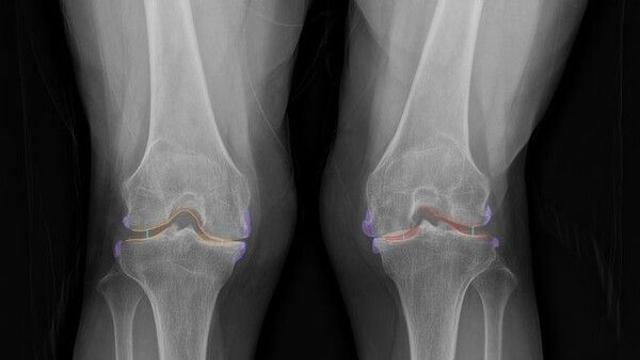

"무릎 악화 정도 한눈에"…10초만에 관절염 찾아내는 AI[빠정예진]